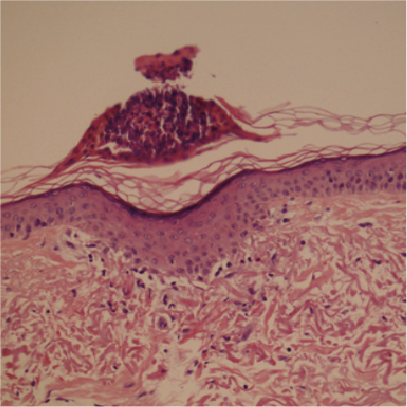

而接受療程後第五天,真皮層內的膠原蛋白數量明顯增加, 表皮傷口亦已經癒合。

療程後第五天

病人PG - 療程後5日:良好的癒合,並形成細小的結痂範圍(最大直徑可達0.25毫米) 結痂下面有被改變了的膠原蛋白 (高達0.20毫米)

病人PG

良好的癒合,

並形成細小的結痂範圍

(最大直徑可達0.25毫米)

結痂下面有被改變了的膠原蛋白

(高達0.20毫米)